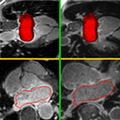

The registration is delivered as a Extension module for Slicer3. It can be installed from the Extension manager. Below in Figure R1 we show the GUI of the module. We need to feed the pre/post-MRI and pre/post-Endocardium images. The module then compute the registration from the post-op MRI to the pre-op MRI.

GUI and one case screenshot